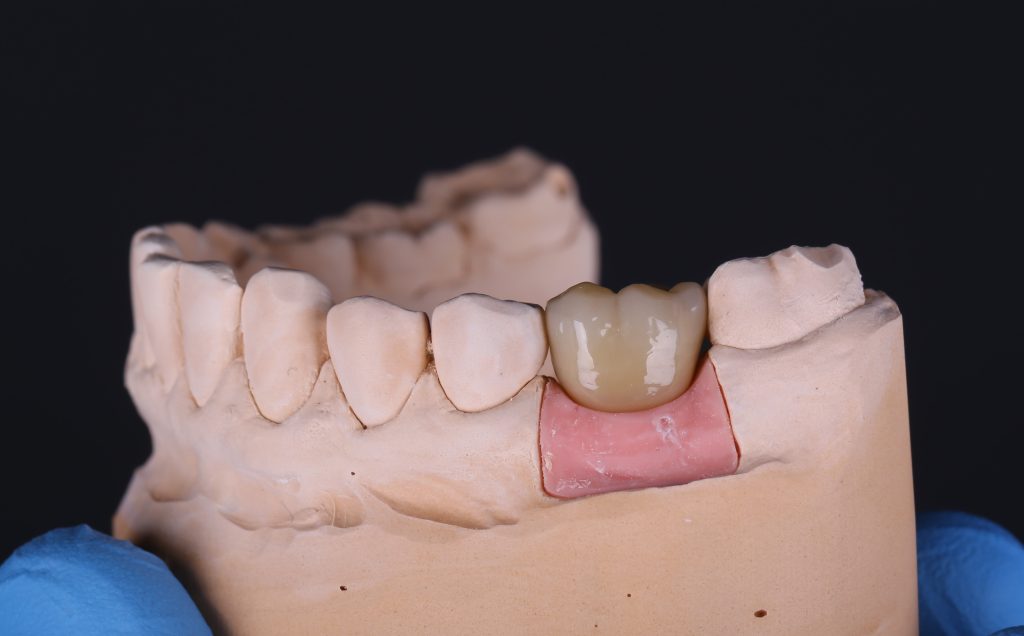

Вид готовой ортопедической конструкции